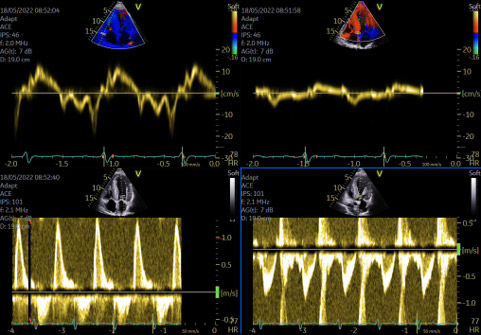

Figure 2 : Paramètres échocardiographique pour évaluer les pressions de remplissage

- Évaluation des pressions de remplissage (Figure 3), qui permet d’aider à adapter les doses de diurétiques ;

- Évaluation de la fonction ventriculaire gauche par étude du strain global longitudinal et de son évolution sous traitement ; un strain global longitudinal < 10.4 % implique un pronostic plus sombre, même si la FEVG est préservée ;

- Évaluation du cœur droit (dilatation, strain, épaisseur paroi libre) et des oreillettes : une dysfonction ventriculaire droite (strain de la paroi libre < 17 %) est un critère pronostique péjoratif fort ;

- Étude du strain atrial gauche, qui, < 13 % pendant la systole ventriculaire (phase réservoir), est aussi un facteur pronostique majeur, corrélé à la sévérité des symptômes, au risque thrombo-embolique, et à l’apparition d’arythmies atriales (Figure 4)4,5.